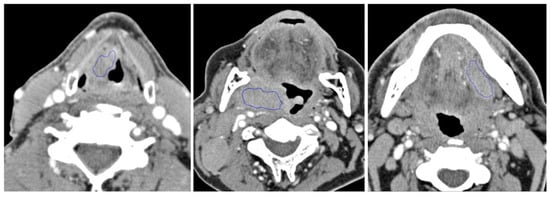

2. Materials and Methods

2.1. Patients & Inclusion Criteria

2.2. Image Acquisition